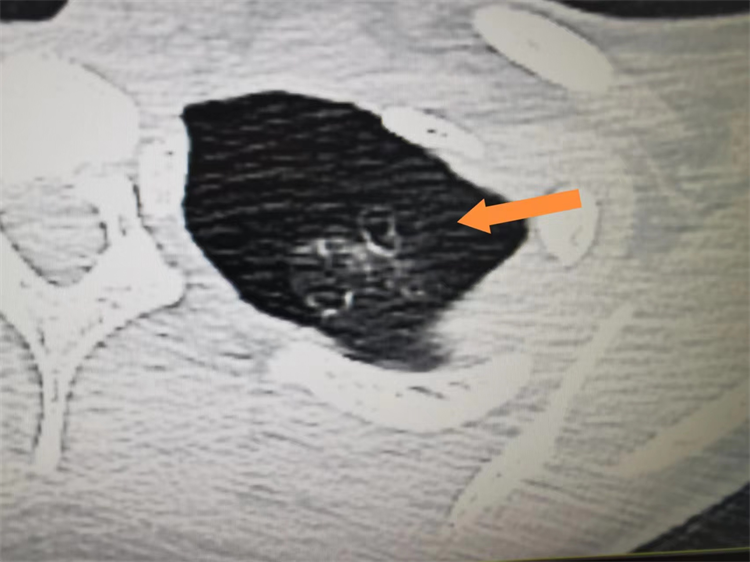

16岁患者叶女士因突发胸痛伴呼吸困难前往福田区第二人民医院就诊,来院时呈痛苦面容、呼吸急促、胸闷、胸痛不适,经急诊胸部CT结果显示,患者左侧自发性气胸,左肺气胸压缩约50%。在办理住院手续后,胸外科贾涛主任立即为患者进行胸腔闭式引流术,引流后患者呼吸功能恢复,胸闷胸痛的症状缓解。但是停止胸腔引流后,患者胸闷胸痛的症状再次出现,经胸部CT检查发现,患者再次出现了自发性气胸的情况。经科内讨论,患者此次自发性气胸的原因是由于患者肺大疱破裂导致,由于破口较大,自行愈合可能性小,且复发率高,建议其进行肺大疱切除+胸膜固定术,以达到根治性切除。叶女士及其家属了解清楚病情及手术方式后,对医院和医生充分信任并且决定治疗。